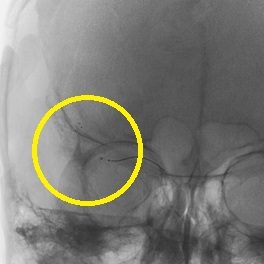

ソリティア(ステント型血栓除去器具)による超急性期血管内治療

突然の意識障害と左半身重度麻痺で発症した右内頚動脈閉塞例。発症から 5 時間が経 過しており、t-PA 治療の適応外であったため緊急で血管内治療を施行。治療開始後速やかに完全再開通を得た。術後左麻痺は残存したが意識障害は回復。